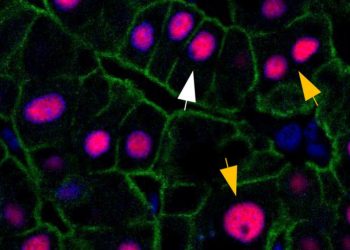

Descubren un nuevo tipo de coronavirus en roedores que puede infectar a humanos

2022-06-07 Un grupo de investigadores ha encontrado un nuevo tipo de coronavirus que se propaga entre...